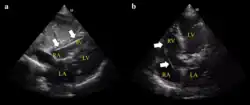

- Ultrasound showing the device in the right ventricle

- Example of ECG off the device a) free floating in the RV b) in contact with the RV wall

- It is possible to place the lead in the coronary sinus, normal (left) dilated (right). Such placement is okay.